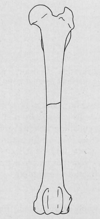

- Bone scans → lameness evals

What agent is used for bone scans?

MDP

(Methyline Di-Phosphate)

What does MDP bind to in bones?

hydroxyapatite crystals

What is MDP localization in bone dependent on?

Depends on the rate & extent of bone remodelling and blood perfusion

List the 3 Imaging Phases of a Bone Scan.

- Phase I: Vascular or pool phase

- Phase II: Soft tissue phase

- Phase III: Bone phase

Characteristics of the Vascular phase of a bone scan?

- Area imaged = vasculature & extravascular fluid

- Very short phase

- Only 1 area can be imaged

- Best real-time

Characteristics of the Soft tissue phase of a bone scan.

- Distributed in the ECF of all body tissues

- Occurs 1- 15 min post injection

Characteristics of the Bone phase of a bone scan.

- IDs pathological increases in blood flow & bone pathology

- Occurs 2-4 hrs. post injection

What is a “hot spot” on Scintigraphy?

An area of increased uptake =

increased bone/soft tissue activity